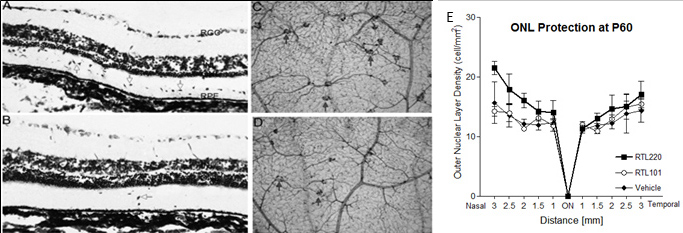

Figure 1. Retinal protection by RTL220 therapy. RTL220 therapy protects RCS retina from degeneration. A, B: Increased number of the outer nuclear layer rows was observed after RTL220 treatment (B) compared to RTL101 treatment (A) at P60 with RTL220 (200 μg/dose) treatment stared at P21 (the onset of degeneration); the retinas were stained with cresol

violet. Arrows point at migrating cells to the outer retina (ganglion cell layer [GCL], retinal pigment epithelium [RPE]).

C, D: Representative vascular pathology is shown for retinal whole mounts collected at P90 and stained with nicotinamide adenine

dinucleotide phosphate (NADPH)-diaphorase to identify vascular complexes (arrows). Photomicrographs are showing the vascular

complexes from middle part of a control retina (C) and dramatically reduced in RTL220-treated rats (D). E: Outer nuclear layer (ONL) protection was present at P60 with RTL220 (100 μg/dose) treatment stared at P30 (degeneration

has begun). Graphs represent nuclei density counts from RTL treatments started at P30 and performed till P60 treated with

RTL220; measurements of the ONL density at cells/mm2 were determined from histological sections from each treatment group and were recorded at 0.5, 1.0, 1.5, 2.0, 2.5, and 3

mm from the optic disc region. The error bars represent SEM (n=6; p=0.041).